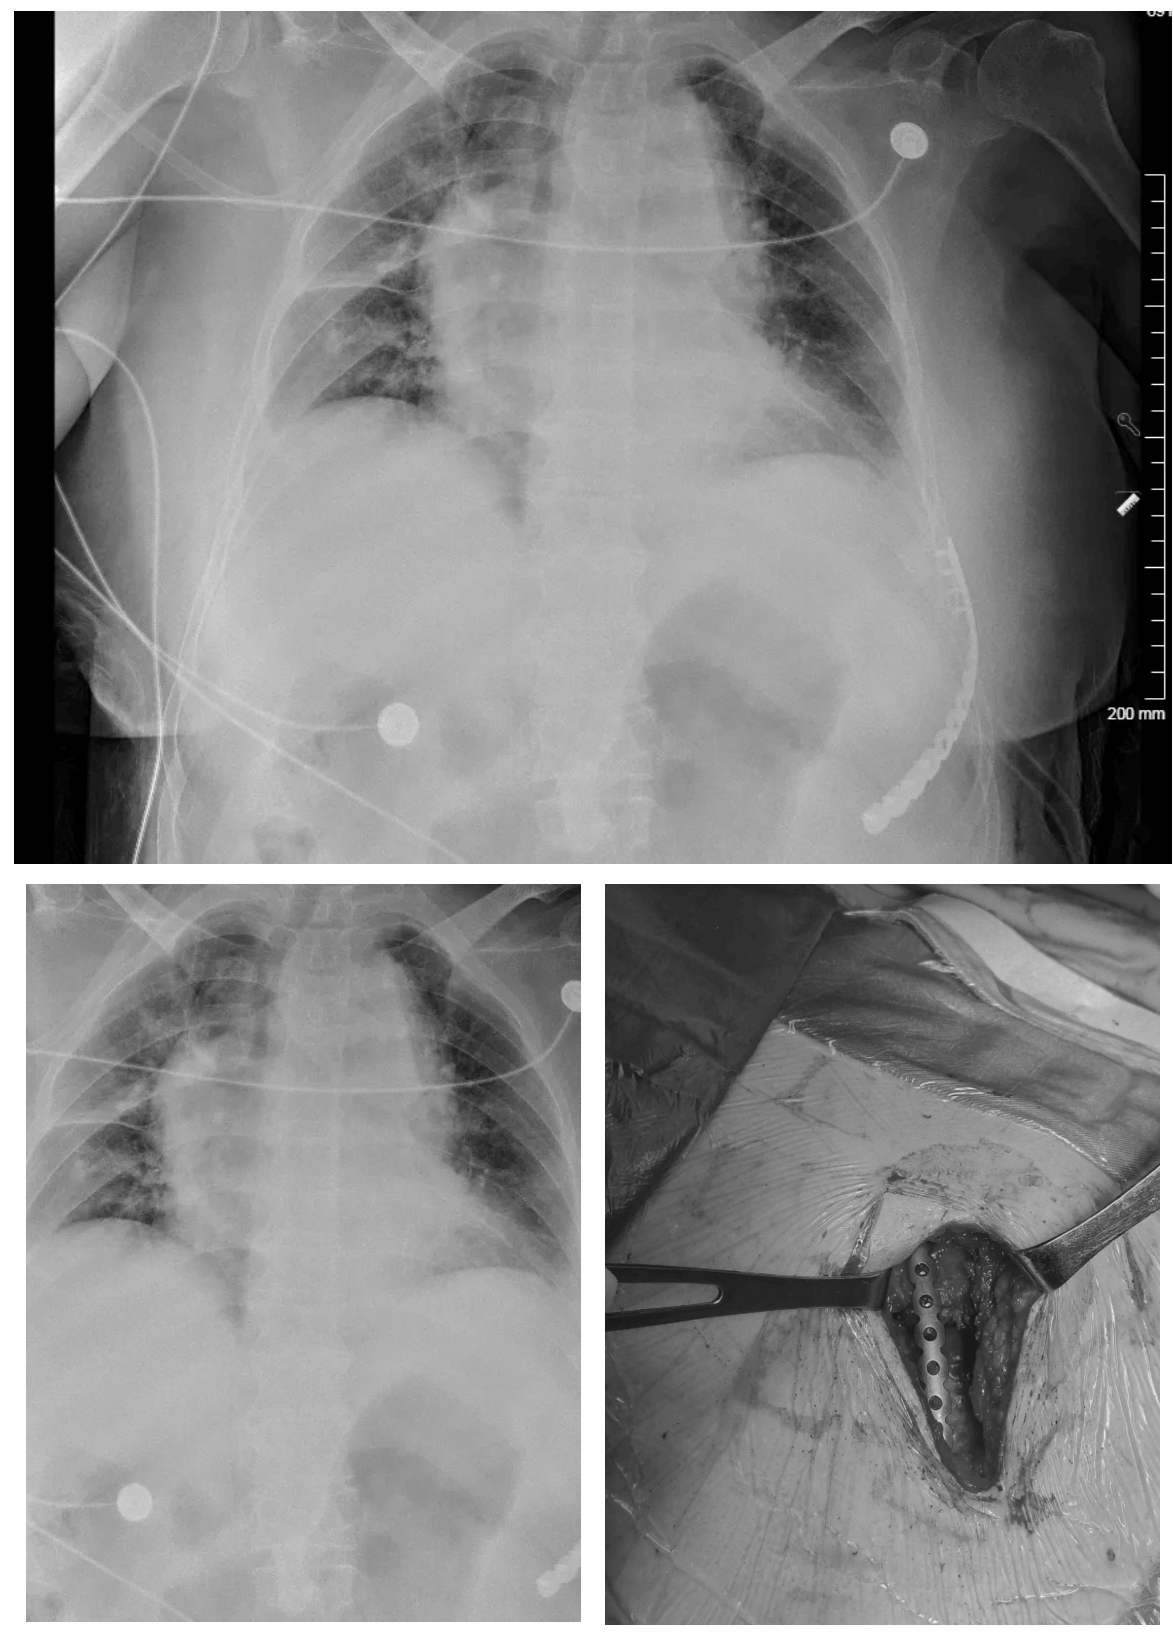

在2023年10月开展肋骨骨折内固定手术,至2025年4月已完成百例的胸壁骨折固定术。虽然仅有百例,但在北京乃至全国完成的数量及速度都是遥遥领先。在这一年半的时间里,与上海六院及积水潭医院进行充分的合作及学习,早些年一年仅能做不到20例的环抱器肋骨骨折内固定术,由于技术的壁垒,大多数肋骨骨折患者转诊至其他医院或者强行要求保守治疗,很大程度上增加了患者的痛苦,没有从根本上为患者解决问题。

内固定系统的应用,使肋骨骨折上升到了一个新的高度。利用螺钉钢板系统及微创内窥镜系统,整个胸壁的肋骨都可以进行固定,大大拓宽了手术适应症,充分解决了患者的需求。新技术需要学习曲线,门槛较高,但是入门后上手很快。后续细节上需要精益求精,如何减小患者的伤口,如何定位准确找到准确的骨折点,如何利用小切口固定更多的肋骨,如何降低患者术后的疼痛。这些也都成了教学和科研很好的方向。

同时在处理重症胸外伤患者上也不断进行挑战,成功救治了一名肋骨骨折合并急性肺栓塞的患者。成功救治了一名双侧多发肋骨骨折、胸骨骨折,汽车碾压伤的患者。还成功救治了一名车祸撞击伤,胸骨分离,双侧肋骨粉碎性翻转骨折的患者,对该患者进行了胸壁整体的重建,效果非常满意。患者体重200斤,手术操作十分困难,术后恢复良好,可以自主下地行走。还救治过高龄90岁的老人,术后康复出院,可生活自理。通过肋骨内固定技术,还可以进行多种肋骨肿瘤的救治及胸廓重建术。